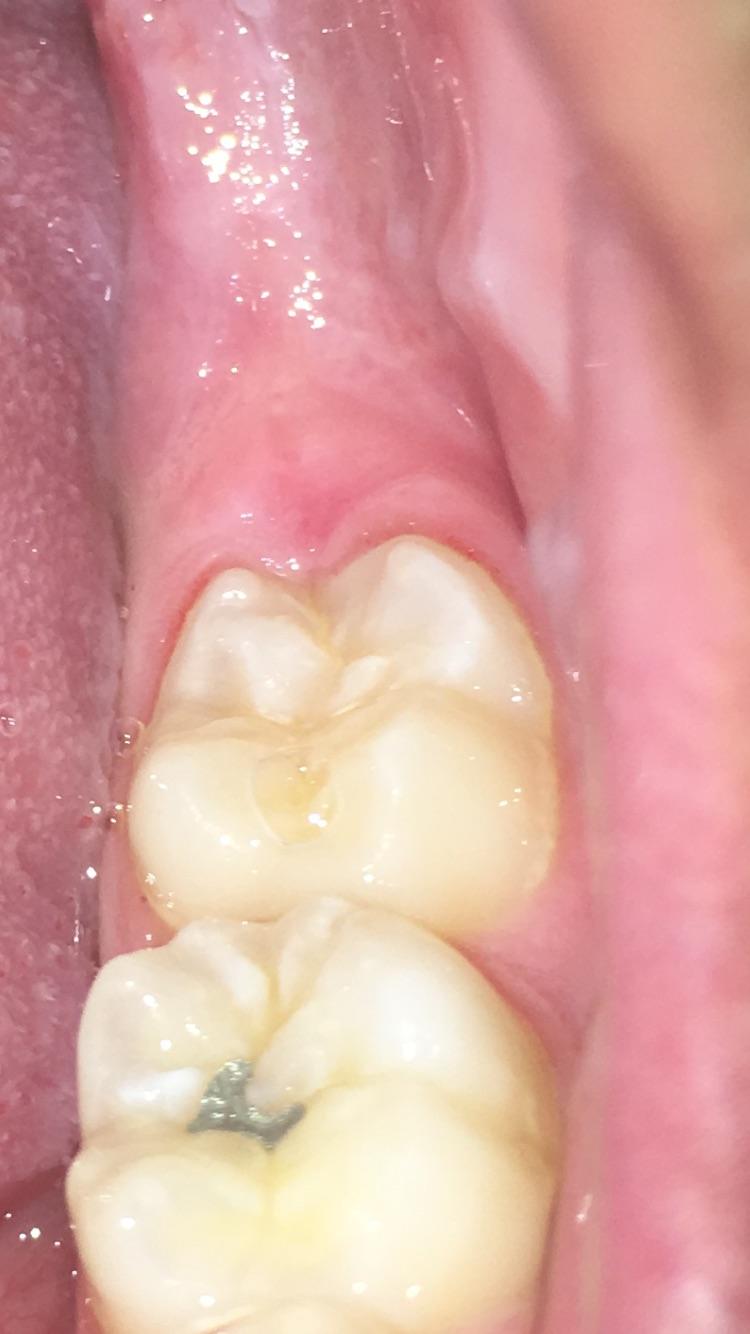

Swollen Gum Around Wisdom Tooth Pain Relief . Symptoms can include pain, swelling, discharge, and. You may also have a swollen, painful gum around your wisdom tooth, or even taste or see pus seeping from around the tooth. It’s more common in your lower teeth and it usually happens around. Pericoronitis is a term used to describe inflammation or swelling of the gum tissue surrounding a wisdom tooth. Pericoronitis is an inflammation or swelling of your gum tissue. The lower wisdom teeth tend to be more commonly affected than the upper. Swollen gums around your wisdom tooth can be a sign of a condition known as pericoronitis. Pericoronitis is the inflammation and infection of the gum tissue flap partially. Pericoronitis is inflammation of the tissue surrounding a third molar, otherwise known as a wisdom tooth. It is commonly seen in wisdom teeth that are partially impacted, with only a small portion of the crown seen above the gumline.

Impacted Wisdom Tooth Due To Which a Gum Hood Was Formed. Inflammation Swollen Gum Around Wisdom Tooth Pain Relief The lower wisdom teeth tend to be more commonly affected than the upper. You may also have a swollen, painful gum around your wisdom tooth, or even taste or see pus seeping from around the tooth. Swollen gums around your wisdom tooth can be a sign of a condition known as pericoronitis. Pericoronitis is an inflammation or swelling of your. Swollen Gum Around Wisdom Tooth Pain Relief.